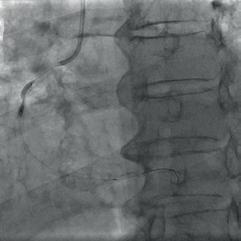

mospheres, the balloon ruptured, resulting in abrupt vessel occlusion and haemodynamic deterioration of the patient with hypotension and bradycardia. After medical stabilisation, flow was partially restored through the RCA with a clearly visible large dissection flap in the middle portion of the vessel (Fig. 2c). The patient was clinically stabilised and the procedure was terminated. A few months later we decided to do a second procedure. This time we found a marked deterioration of the RCA, which was critically stenosed in a mid-portion. After a difficult wire crossing, multiple dilations were performed with different semi-compliant and non-compliant balloons throughout the RCA (Fig. 3a). We then decided to treat the lesion with intravascular lithotripsy, but the IVL balloon failed to cross the lesion. Subsequently,

the entire middle RCA was treated by multiple dilations with smaller OPN NC balloons (2.0  15 mm and 2.0  10 mm, applied >30 inflations at 35 – 40 atmospheres) in order to create space for IVL balloon delivery. After these aggressive dilations, a 3.0  12 mm IVL balloon (Skockwave) was finally advanced and multiple (80 in total) intravascular pulses were delivered throughout the middle RCA (Fig. 3b) with improved angiographic appearance. After partial dissection of the severely calcified stenosis, we performed additional inflation with non-compliant 2.5  15 mm and 3.0  20 mm balloons (Fig. 3c) and finally achieved a satisfactory result.